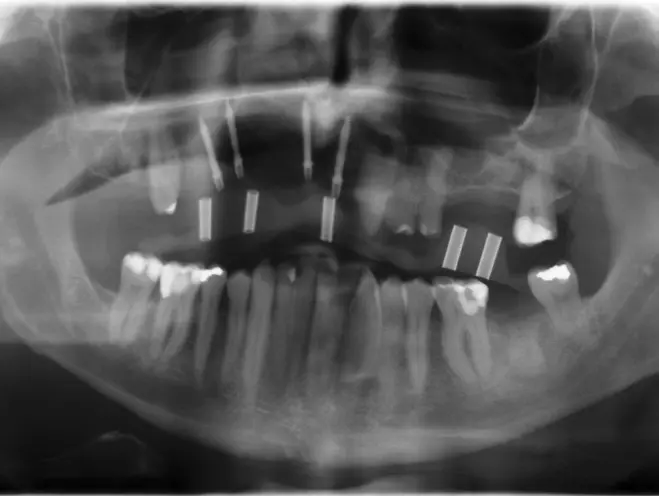

Nach Freilegung der Implantate regio 026,027 im Februar 2020, bei der auch die Implantation regio 037 (T3, Zimmer Biomet Dental, 4,0 mm x 13,0 mm) vorgenommen wurde (Abb. 32 OPG nach Freilegung), erfolgte im März nach Abformung mit offenem Löffel (open tray technique) und Gesichtsbogenregistrat die prothetische Versorgung mittels CAD/CAM gefräster Abutments (Dentaltechnik Hessel und Lutgen, Trier) und transversal verschraubter, verblockter VMK-Kronen (Abb. 33-36). Die Freilegung und Versorgung des Implantates 037 ist zusammen mit der Entfernung des Zahnes 38 für Juli 2020 geplant.